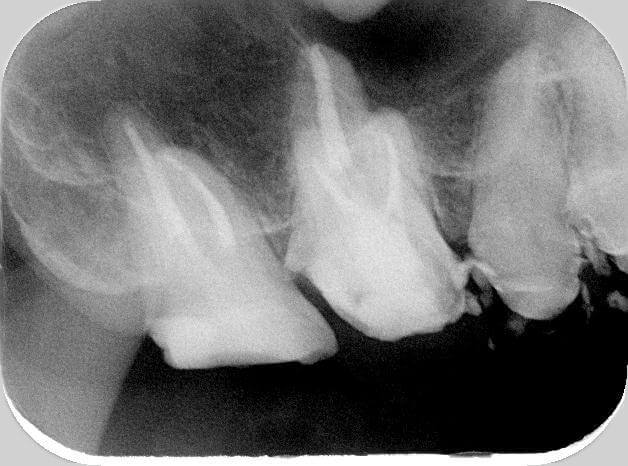

矯正歯科・噛み合わせ治療